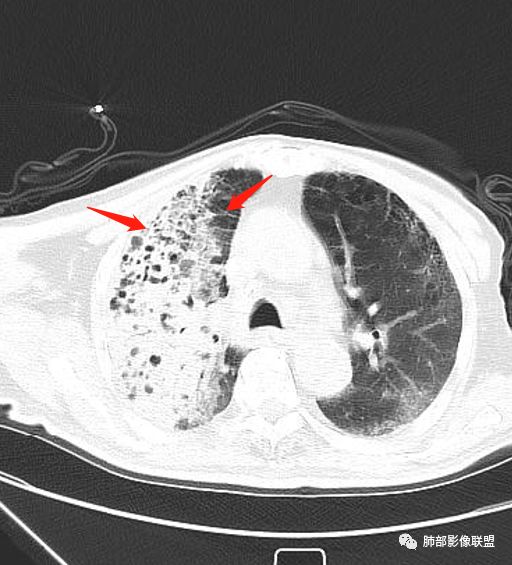

王秀仙:

右肺上叶大片实变,其内可见虫蚀样空洞及扩张支气管,其中一空洞内可见曲菌球样结构,右肺体积略缩小。老年糖尿病患者,慢阻肺背景,考虑右肺上叶干酪性肺炎并曲霉感染。

老年男性,糖尿病患者,右上肺大片实变,内可见多发虫蚀样空洞,右尖段近胸膜处一空洞内可见一类圆形结节影,支气管扩张,淋巴结肿大,双下肺索条,胸膜增厚。结合糖尿病病史,首选考虑结核干酪性肺炎合并曲霉菌感染,待排肺炎型肺癌

老年男性,糖尿病基础,有咳嗽,喘累症状,病程10天,右上肺大片实变,内虫嗜样,无壁空洞,支气管壁增厚,扩张,淋巴结肿大,胸膜增厚,考虑干酪性肺炎,鉴别粘液腺癌。

老年男性,糖尿病病史,慢性病程,右胸廓塌陷,右肺沿支气管分布实变及GGO,叶段分布趋势,其内见支气管充气征及虫蚀样空洞,周围间质受累,指向气道来源病变播散,纵隔淋巴结肿大,密度高伴钙化,综合考虑干酪性肺炎。鉴别肺炎型肺癌。

老年男性,有糖尿病史,右肺上叶大片实变影,有支气管充气征,支气管走行僵直,有扩张,有多发无壁小空洞和俩个稍大空洞,胸膜稍增厚,双下肺野间质性改变,考虑肺结核,干酪性肺炎可能性大。

老年男性,右肺上叶大片实变,边界局部清楚,局部模糊,其内见支气管充气征及多发大小不等的小泡状及分枝状无壁空洞。双肺下叶磨玻璃样间质性改变。综合考虑右肺上叶结核,干酪性肺炎可能。

宇宙星空:

右上肺大片状高密度影,呈蜂窝样改变,部分气腔无壁,部分呈厚壁改变,内部结构紊乱,部分边缘GGO边界清楚,大小不一,病灶近端小远端大,近端支气管壁增厚,支持感染性病变,考虑结核,其内支气管呈枯树枝改变,病灶局部膨隆,内部结构紊乱,边界的GGO部分清楚,恶性(腺癌)待排。